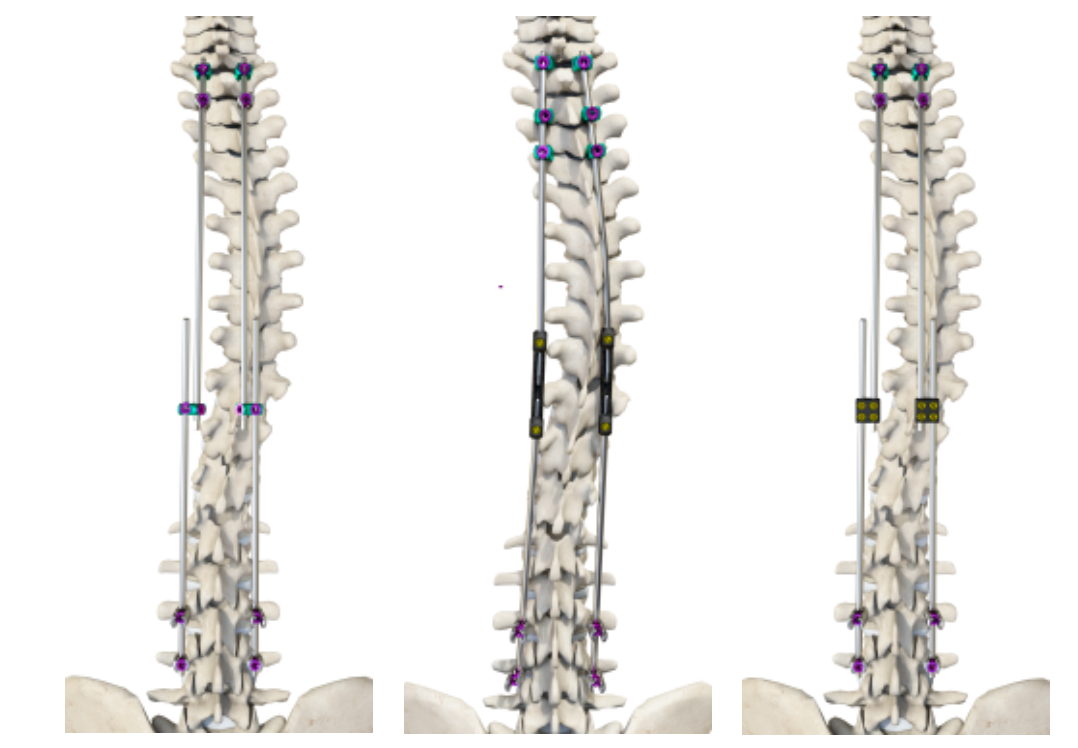

經(jīng)與眾多國內(nèi)頂級專家團(tuán)隊(duì)深入溝通,不斷創(chuàng)新,目前我司已形成了覆蓋全年齡、全術(shù)式的脊柱畸形解決方案。

德康醫(yī)療脊柱畸形解決方案

覆蓋全年齡段的內(nèi)固定系統(tǒng):

豐富的配件系統(tǒng)——生長閥:

根據(jù)患者情況選擇合適的生長閥技術(shù),為臨床提供更多個性化選擇。